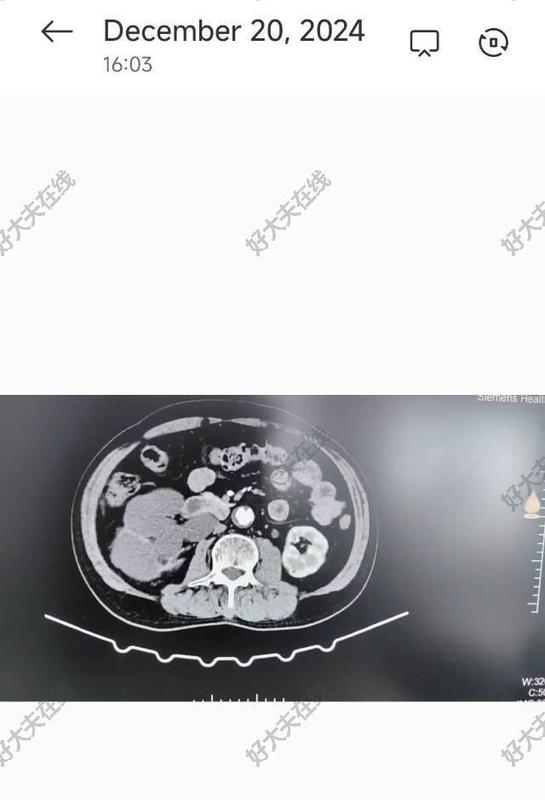

- 精選 腎積水

治療前患者因長期輸尿管結石梗阻引起腎積水(重度),最終腎萎縮,形成無功能腎。另外,合并了右頸內(nèi)動脈閉塞。治療中行腹腔鏡下切除右側無功能腎,微創(chuàng)手術下順利切除,出血不足20ml治療后治療后即刻有出現(xiàn)腰痛,結石引起梗阻導致腎積水的,需及時解除梗阻,避免腎功能進一步惡化

隨著社會的發(fā)展,生活習慣和環(huán)境的改變,和其他疾病一樣,泌尿系統(tǒng)腫瘤的發(fā)病率也越來越高。近日,一名72歲男性(左側輸尿管癌)患者在清遠市清城區(qū)人民醫(yī)院實施了完全腹腔鏡下左輸尿管癌根治術,日前患者恢復良好出院。 手術只在患者腹部切開4個1厘米左右的“鑰匙孔”,用腹腔鏡配合下腹部小切口,成功切除了左側的腎臟、全段輸尿管和部分膀胱,術中出血僅約為20毫升,手術順利結束。 輸尿管癌切除一般采用傳統(tǒng)手術方式,手術范圍大,切口約15-30厘米,術中組織損傷重,出血較多,患者恢復慢。而腹腔鏡下微創(chuàng)手術,僅需在患者腹部或腰部開3~4個1厘米左右的“鑰匙孔”,再配合下腹部小切口即可完成手術。手術切口小,分離及切割組織精細,組織損傷小,術中出血少,術后恢復快,治療效果好。 溫馨提示:提醒廣大市民朋友,血尿是泌尿系統(tǒng)疾病中最常見的癥狀之一,也是泌尿系統(tǒng)腫瘤的常見表現(xiàn),尤其是老年人要注意觀察尿液情況,如出現(xiàn)肉眼可見的紅色尿液,應引起高度重視,甚至部分腎腫瘤常無明顯癥狀,建議定期常規(guī)泌尿系彩超體檢,若有不適及時到醫(yī)院檢查,做到早發(fā)現(xiàn)早治療。 輸尿管癌梗阻引起腎積水